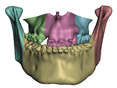

2.5.1. Bones

- In maxillary procedures, the maxilla is separated from the skull through a Lefort osteotomy, classified based on its anatomical level. In this cohort, the distribution of cases is: 8 Lefort I cases and 1 Lefort II case; one patient did not undergo maxillary surgery. Moreover, after a Lefort I osteotomy, the maxilla may be segmented (typically into three fragments) in order to expand the upper arch. Maxilla segmentation was applied to 6 patients in this cohort.

- In mandibular procedures, the mandible may be sagittally split on both rami (bilateral sagittal split osteotomy, BSSO) or only one ramus (unilateral sagittal split osteotomy, USSO). In this cohort, the distribution of cases is: 7 BSSO cases, 1 USSO case; two patients did not undergo mandibular surgery. Additionally, a chin osteotomy or genioplasty may be also performed. Genioplasty was applied to 1 patient in this cohort.

- Segmentation of the maxilla and mandible. For all patients, the highest error (except for the neck, which is not clinically relevant as discussed above) appears near the cut areas, both of the maxilla (e.g., patients M5 and M7) and the mandible (e.g., patients M1 and M3). This is probably due to the presence of fixation plates and/or bone grafts in the real result (e.g., patient M10, whose maxilla was not segmented, but where the presence of bone graft has been confirmed by the surgeon who carried out the intervention). As a consequence, patients with a segmented maxilla and/or mandible show in general larger error than those without segmented bones. However, the smooth coupling method proposed in Section 2.3.3 reduces considerably the error in cut areas, as shown in Figure 2.